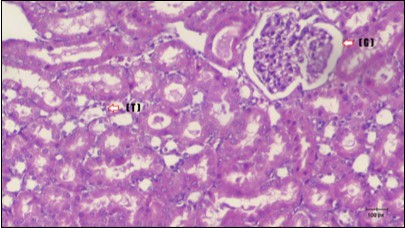

Kidney Histopathological Observations

Kidney sections of diabetic rats showed an increase in mesangial cell and matrix of glomeruli with increase in glycogen deposition and hyalinization of arterioles with thickened basement membranes of proximal and distal convoluted tubules. These changes will lead to progressive reduction in the filtration surface of the glomeruli 35. Histological examination of the kidney of the control rats showed normal structure of renal glomerular. The proximal and distal tubules were lined with normal epithelium (Figure 13). The diabetic rats showed tubular casts, inflammatory cellular infiltration and glomerular atrophy (Figure 14). Kidney of rats in groups (3 and 4) showed some glomeruli return to be normal (G). Focal tubules casts (T) in Fenugreek group and some normal tubules in the Glimepiride group with no inflammatory cellular infiltrate in both groups (Figure 15 and Figure 16). However, kidney of rats in group (5) showed normal glomerular (G), normal tubules (T) with no tubular casts (Figure 17).

Figure 13.photomicrogragh of kidney section of control rat showing normal rounded Bowman,s capsules with normal glomeruli (arrow) ,round proximal tubules (dash-arrow) and elongated distal tubules with high cuboidal cells (star) . (H&E) (40X)

Figure 14.Photomicrogragh of kidney section of diabetic rat showing a trophy of Bowman,s capsules and damage of glomeruli (arrow) and damage of distal and proximal tubules with congested blood vessels (star) . (H&E) (100Px).

Figure 15.Photomicrogragh of kidney section of treated rat with Fenugreek showing improvement of Bowman,s capsules with normal glomerular (arrow) and nearly return of distal tubules (dashed –arrow) and proximal tubules (star) (H&E) (40xX).

Figure 16.Photomicrogragh of kidney section of treated rat with Glimepiride showing improvement of Bowman,s capsules and partial improvement of glomerulir (arrow) and completely return of distal tubules and proximal tubules to the normal shape with wide urinary space. (H&E) (40X).

Figure 17.Photomicrogragh of kidney section of treated rat with both Fenugreek and Glimepiride showing improved cortical tissue with most of both Bowman,s capsules (arrow) and proximal tubules (dash-arrow) with nearly normal structure .Note distal tubules still suffering (star). (H&E) (40X).